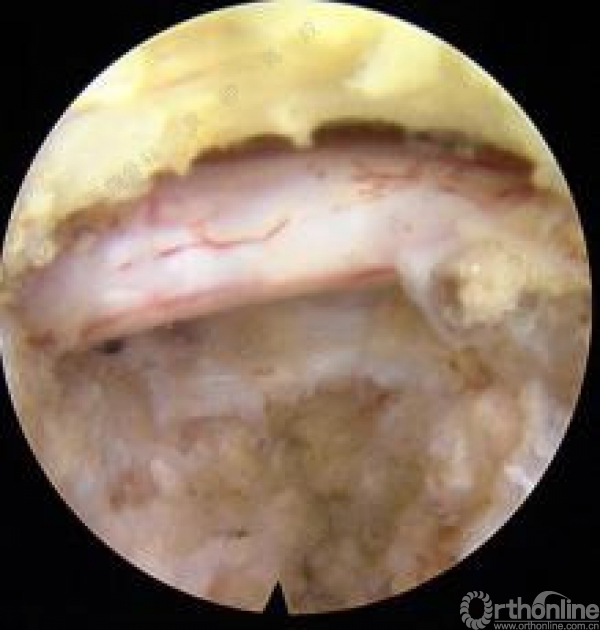

优先处理近端间隙,尤其是近端椎间盘突出的较大时或脱垂超过椎弓根平面者,有累及囊内未发出的下位神经根可能,即一个椎间盘引发多个神经根症状。如果近端间隙处理后患者症状缓解彻底,对远端间隙可不予处理,减少病人创伤的同时也能减少医生的X线暴露。操作时于穿刺点应用1%利多卡因局部麻醉,透视下穿刺至病变节段下位椎体上关节突尖部,置入导丝后扩张管道逐级扩张,依据不同扩张管道应用配套环锯或骨钻磨除上关节突腹侧部分骨质直至椎管外边界,置入工作管道,确定工作管道位于椎管内,置入内窥镜探查。如果关节突骨性结构仍对神经根显露构成阻碍,内镜监视下动力磨钻对其适度扩大,切除部分外侧纤维环及黄韧带后探查神经根并摘除致压物。术中神经根周围减压时如出现神经根激惹现象,及时询问患者能否复制术前疼痛。完成一个间隙减压后询问患者疼痛及麻木缓解程度,并配合神经根牵拉试验检查手术效果,如患者仍感症状未完全缓解,拔出内镜及管道再次行远端间隙手术。手术结束后缝合伤口,再次询问患者神经症状缓解情况并再次行神经根牵拉试验证实手术效果。